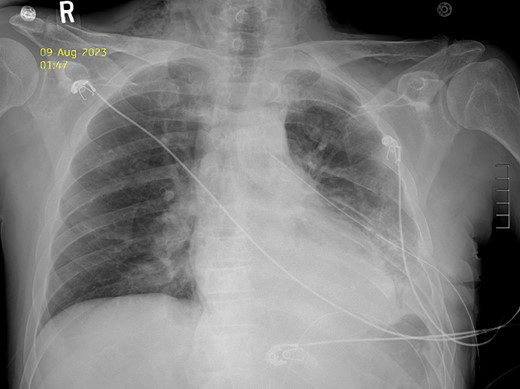

Thirty-seven days after the initial visit, the patient returned to the emergency department with burning epigastric pain that radiated to the left upper chest and hematemesis. Vital signs revealed tachycardia and hypertension. A comprehensive physical exam was significant for decreased breath sounds at the left base and tenderness in the left upper quadrant without signs of peritonitis. Pertinent laboratory findings showed leukocytosis with a left shift and thrombocytosis. A chest X-ray showed a significant portion of the gastric body in the left hemithorax (Fig. 1). A pulmonary CT angiogram found segmental and subsegmental pulmonary emboli in both lungs with no evidence of right heart strain and a left pleural effusion. A left diaphragmatic hernia with the “dangling diaphragm” sign can be seen on the sagittal view (Fig. 2). The coronal view shows discontinuity of the diaphragm and the “collar” sign (Fig. 3); the axial view shows the “dependent viscera” sign and thoracic fluid abutting abdominal viscera (Fig. 4).

Postoperative Day 2 chest X-ray showing reduced diaphragmatic hernia and resolving pleural effusion.